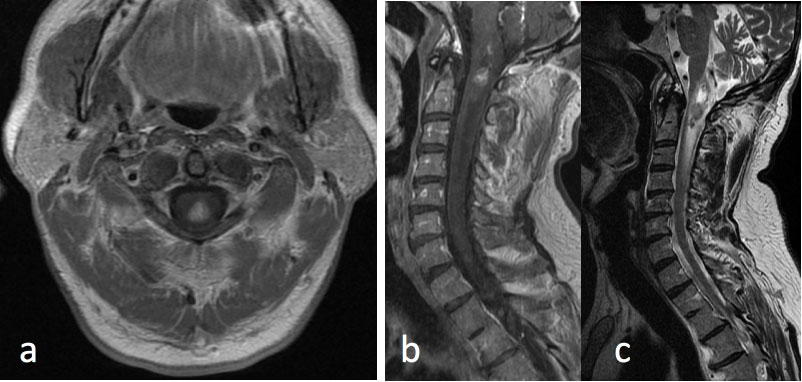

- MRI of the brain and spine